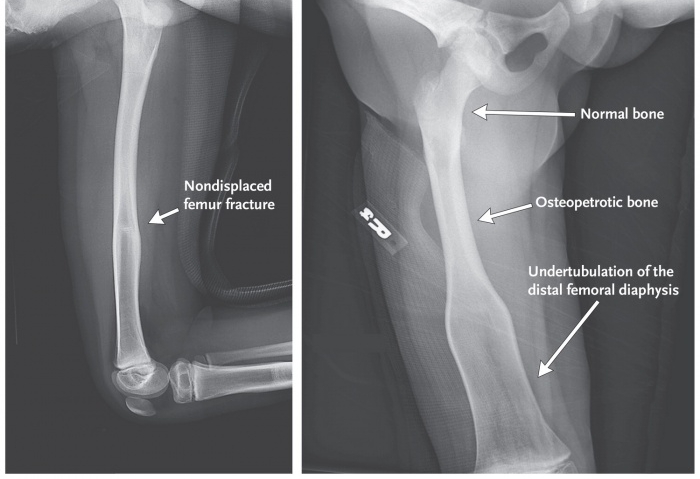

Диагностика остеопетроза представляет собой сложный процесс, требующий внимательного подхода со стороны врачей. Это редкое генетическое заболевание, характеризующееся аномальным увеличением плотности костной ткани, что приводит к “мраморному” виду костей. Врачи отмечают, что основными симптомами являются частые переломы, боли в костях и проблемы с нервной системой. Для диагностики используются рентгенография, компьютерная томография и генетическое тестирование, позволяющее выявить мутации в генах, ответственных за формирование костной ткани.

- Рентгенография. Это один из наиболее надежных методов диагностики. На рентгеновских снимках видны изменения в структуре костей, однако канал, содержащий костный мозг, не отображается.

| Рентгенография | Увеличение плотности костей, утолщение кортикального слоя, “мраморный” вид костей, деформации костей | Характерный “мраморный” вид на рентгенограмме отражает патологическое уплотнение костной ткани, приводящее к нарушению кровоснабжения костного мозга и развитию тяжелых осложнений. |